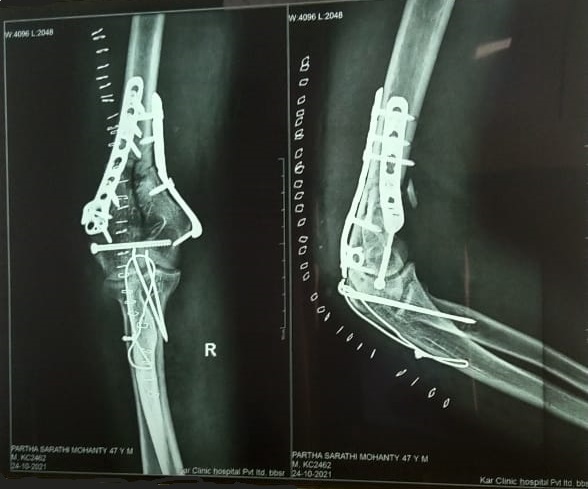

Patient Cases

Post operative treatment of this fracture was done with Laser. The patient is fine with out pain. Driving his car regularly without any complications.